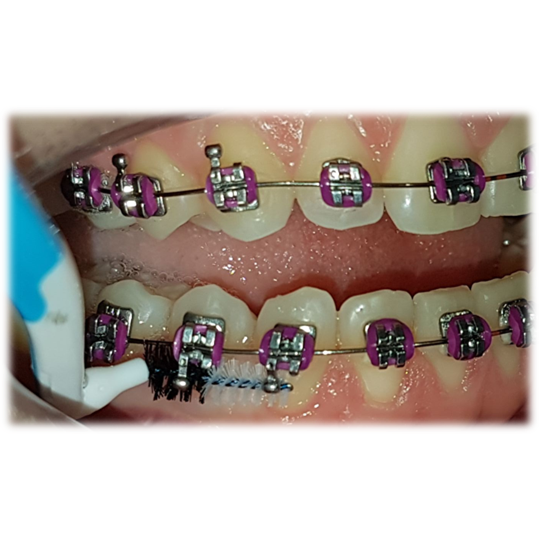

Su uso durante el tratamiento ortodóntico (Fig. 6) trae grandes beneficios ya que los dispositivos de ortodoncia son grandes retenedores de placa. Se aconseja su uso alrededor de los cuatro lados del bracket (Fig. 6) y con especial cuidado bajo tubos bucales (Fig. 7) y hooks (Fig. 8, 9 y 10).